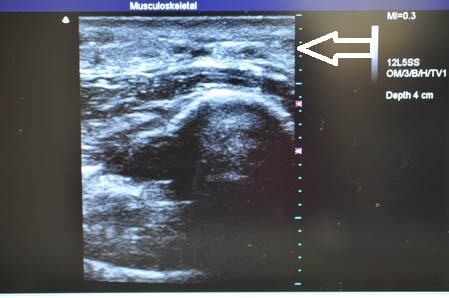

ではいつものように3Dタッチビュー(=超音波)で

皮下脂肪層を確認しながら見ていきましょう。

左ちからこぶ。

↓ ↓ ↓